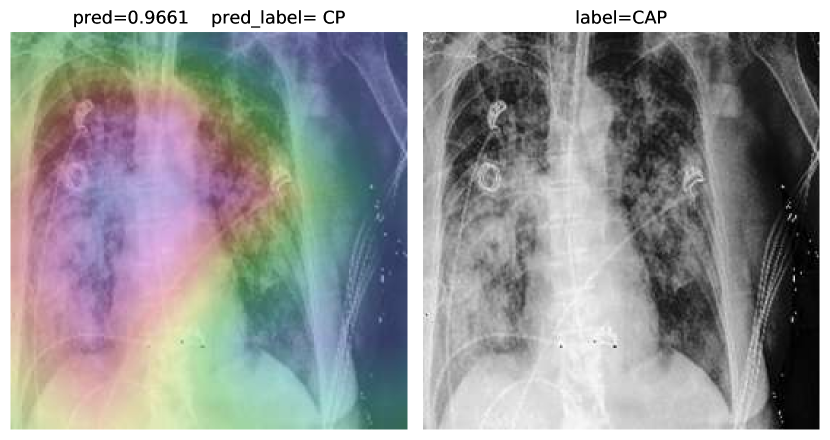

Accuracy score is 81.04%, with f-scores of 0.85 and 0.76 for CP and CAP classes, respectively. In a number of cases, especially in the first stages of virus progression, CP has unilateral findings. Also, CAP may cause bilateral consolidations. Therefore, some cases are expected to be misclassified between CP and CAP. From the confusion matrix, it could be seen that a relatively high number of images are misclassified between CAP and normal. A potential reason for this issue is considered to be related to wrong labeling. Besides, some CAP CXRs are from patients with early-stage disease development. To confirm the model performance, Grad-CAMs are plotted in Fig. 19.

Figure 19: COVID-CXNet multiclass classification visualization results

The model is properly looking at one lobe for detecting CAP and both lobes for CAP and normal images. There are some wrong labels, nevertheless. A figure containing more visualizations is found in Appendix C. To further enhance statistical scores, a hierarchical approach is implemented. In the first level, we classify images into normal and pneumonia classes. In the second level, pneumonia images are categorized into CP and CAP. Final confusion matrix is illustrated in Table 5.